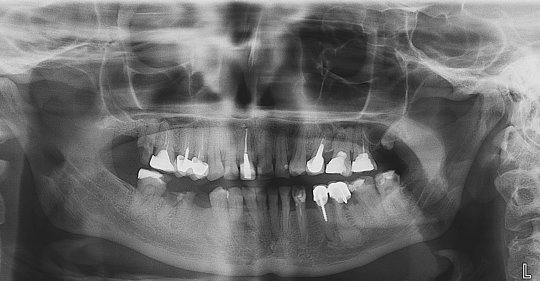

Врач говорит, что нужна имплантация до снятия брекетов, т.е торопит, так ли это важно? Нужна имплантация 2х зубов — вернхняя 7, крайний (с синуслифтингом), нижняя 3, клык с помощью брекетов и пружины раздвинули место под него, если снимут брекеты, не уменьшиться ли это пространство и потом нельзя будет вставить имплантант.

Добрый день. Без снимка сложно судить и давать какие либо рекомендации, но, как правило, имплантацией занимаются после снятия брекет-систем. А цены на операцию абсолютно разные — от 18000 до 26000 в зависимости от системы, плюс цена самого имплантата. Синус-лифтинг в наших клиниках стоит 30000 рублей.

Рекомендую услышать еще одно мнение относительно плана лечения.